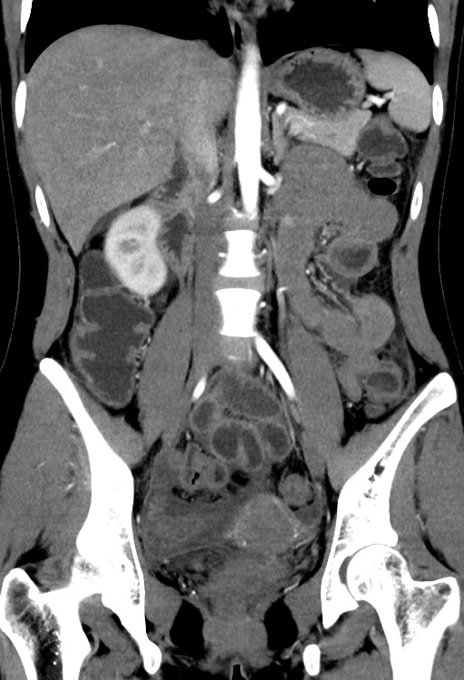

症例17(冠状断像)

【症例】20歳代女性

【主訴】嘔吐、下腹部痛

【現病歴】昨日夕食後に嘔吐し下腹部痛が出現。本日になっても嘔吐持続し改善しないため来院。

【身体所見】意識清明、BT 37.2℃、BP 108/67mmHg、腹部:平坦、やや硬、下腹部正中から右にかけて圧痛あり、反跳痛軽度あり、tapping pain(+)。

【データ】WBC 13600、CRP 14.94